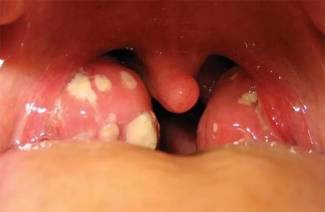

- przy bakteryjnym zapaleniu migdałków na migdałkach widać obfite ropnie, z wirusową postacią choroby - zaczerwienienie gardła, obrzęk węzłów chłonnych, biały nalot;

- białe plamy z bakteryjnym zapaleniem migdałków są zlokalizowane w jamie ustnej gardła, podczas gdy w przypadku wirusowego wykraczają poza wskazane limity.

Zdjęcie pacjenta frustruje wygląd jamy ustnej, gdzie biała płytka zakrywa błonę śluzową będącą w stanie zapalnym, a widoczna jest obecność bolesnych pęcherzyków z dalszym przekształcaniem się we wrzody. Tkanki miękkie są szczególnie wrażliwe na paciorkowce lub inny patogenny wirus, dlatego leczenie należy rozpocząć natychmiast po kompleksowej diagnozie. Główną technikę leczenia przedstawiono poniżej: